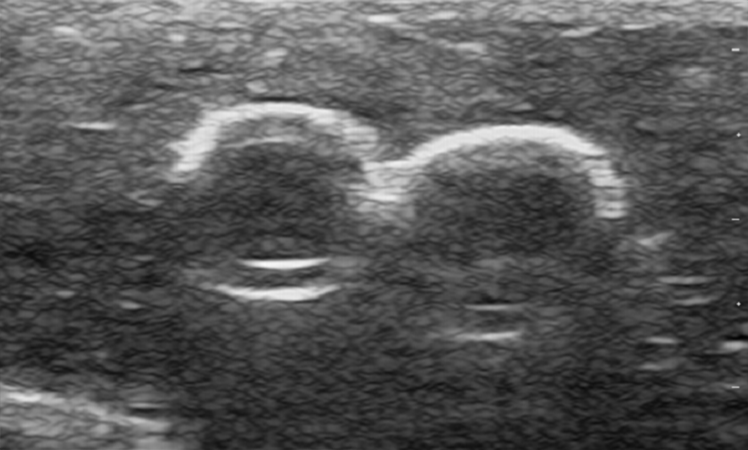

– Compatible with real ultrasound equipment for arterial and venous identification